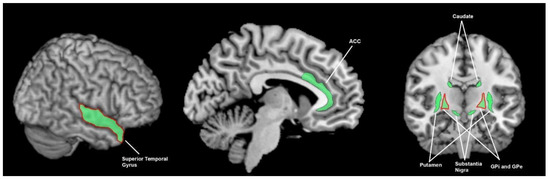

3.3. What Brain Areas Are Involved in Sensory Processing?

3.3.1. What Brain Areas Are Involved in Temporal Processing in Healthy Cohorts?

3.3.2. What Brain Areas Are Found to Function Abnormally in Temporal Processing in People with Parkinson’s Disease?

3.3.3. What Brain Areas Are Involved in Auditory Processing in Healthy Cohorts?

3.3.4. What Brain Areas Are Found to Function Abnormally during Auditory Processing in Patients with Parkinson’s Disease?

3.3.5. What Brain Areas Are Involved in Visual Processing in Healthy Cohorts?

3.3.6. What Brain Areas Are Found to Function Abnormally during Visual Processing in People with Parkinson’s Disease?

3.3.7. What Brain Areas Are Involved in Tactile Processing in Healthy Cohorts?

3.3.8. What Brain Areas Are Found to Function Abnormally during Tactile Processing in Patients with Parkinson’s Disease?

3.3.9. What Brain Areas Are Involved in Proprioceptive Processing in Healthy Cohorts?

3.3.10. What Brain Areas Are Found to Function Abnormally during Proprioceptive Processing in Patients with Parkinson’s Disease?

3.4. The Breadth of Sensory Response and Multisensory Response of the Basal Ganglia